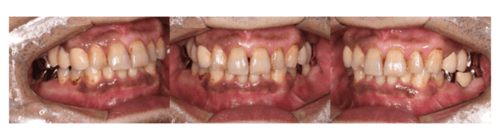

症例3

治療前

治療後(約1週間後)

| 年齢・性別 | 39歳・男性 |

|---|---|

| 主訴 | 上下前歯唇側歯肉の歯肉の色が気になる |

| 治療内容 | 上下顎ガムピーリング |

| 治療費 | 11,000円(2023年2月現在) |

| 治療期間 | 1回30分 |

| リスク・副作用 | ・薬剤の効果により一時的に歯肉が白くなります ・個人差はありますが術後ヒリヒリとした痛みを感じることがあります ・フェノール・アルコール類のアレルギーがある方は行えません ・生活習慣によっては後戻りする可能性があります ・効果には個人差があり色素沈着が深部に浸透している場合は回数がかかることがあります |

| 担当者所見 | タバコをやめたことをきっかけに歯茎を綺麗にしたいと来院されました。 特に下顎右側は長年の喫煙の影響で暗黒色になっており、深部までの沈着は1度ではとりきれないことが予想されました。 しかしピーリング後1週間の状態を見ると、かなり薄色化しており患者様も結果に満足してくださったので1度で終了し今後経過を見ることになりました。 歯茎が綺麗になったことがきっかけでホワイトニングにも興味を持ってくださり今後は歯のクリーニング・ホワイトニングを行なっていく予定です。 |